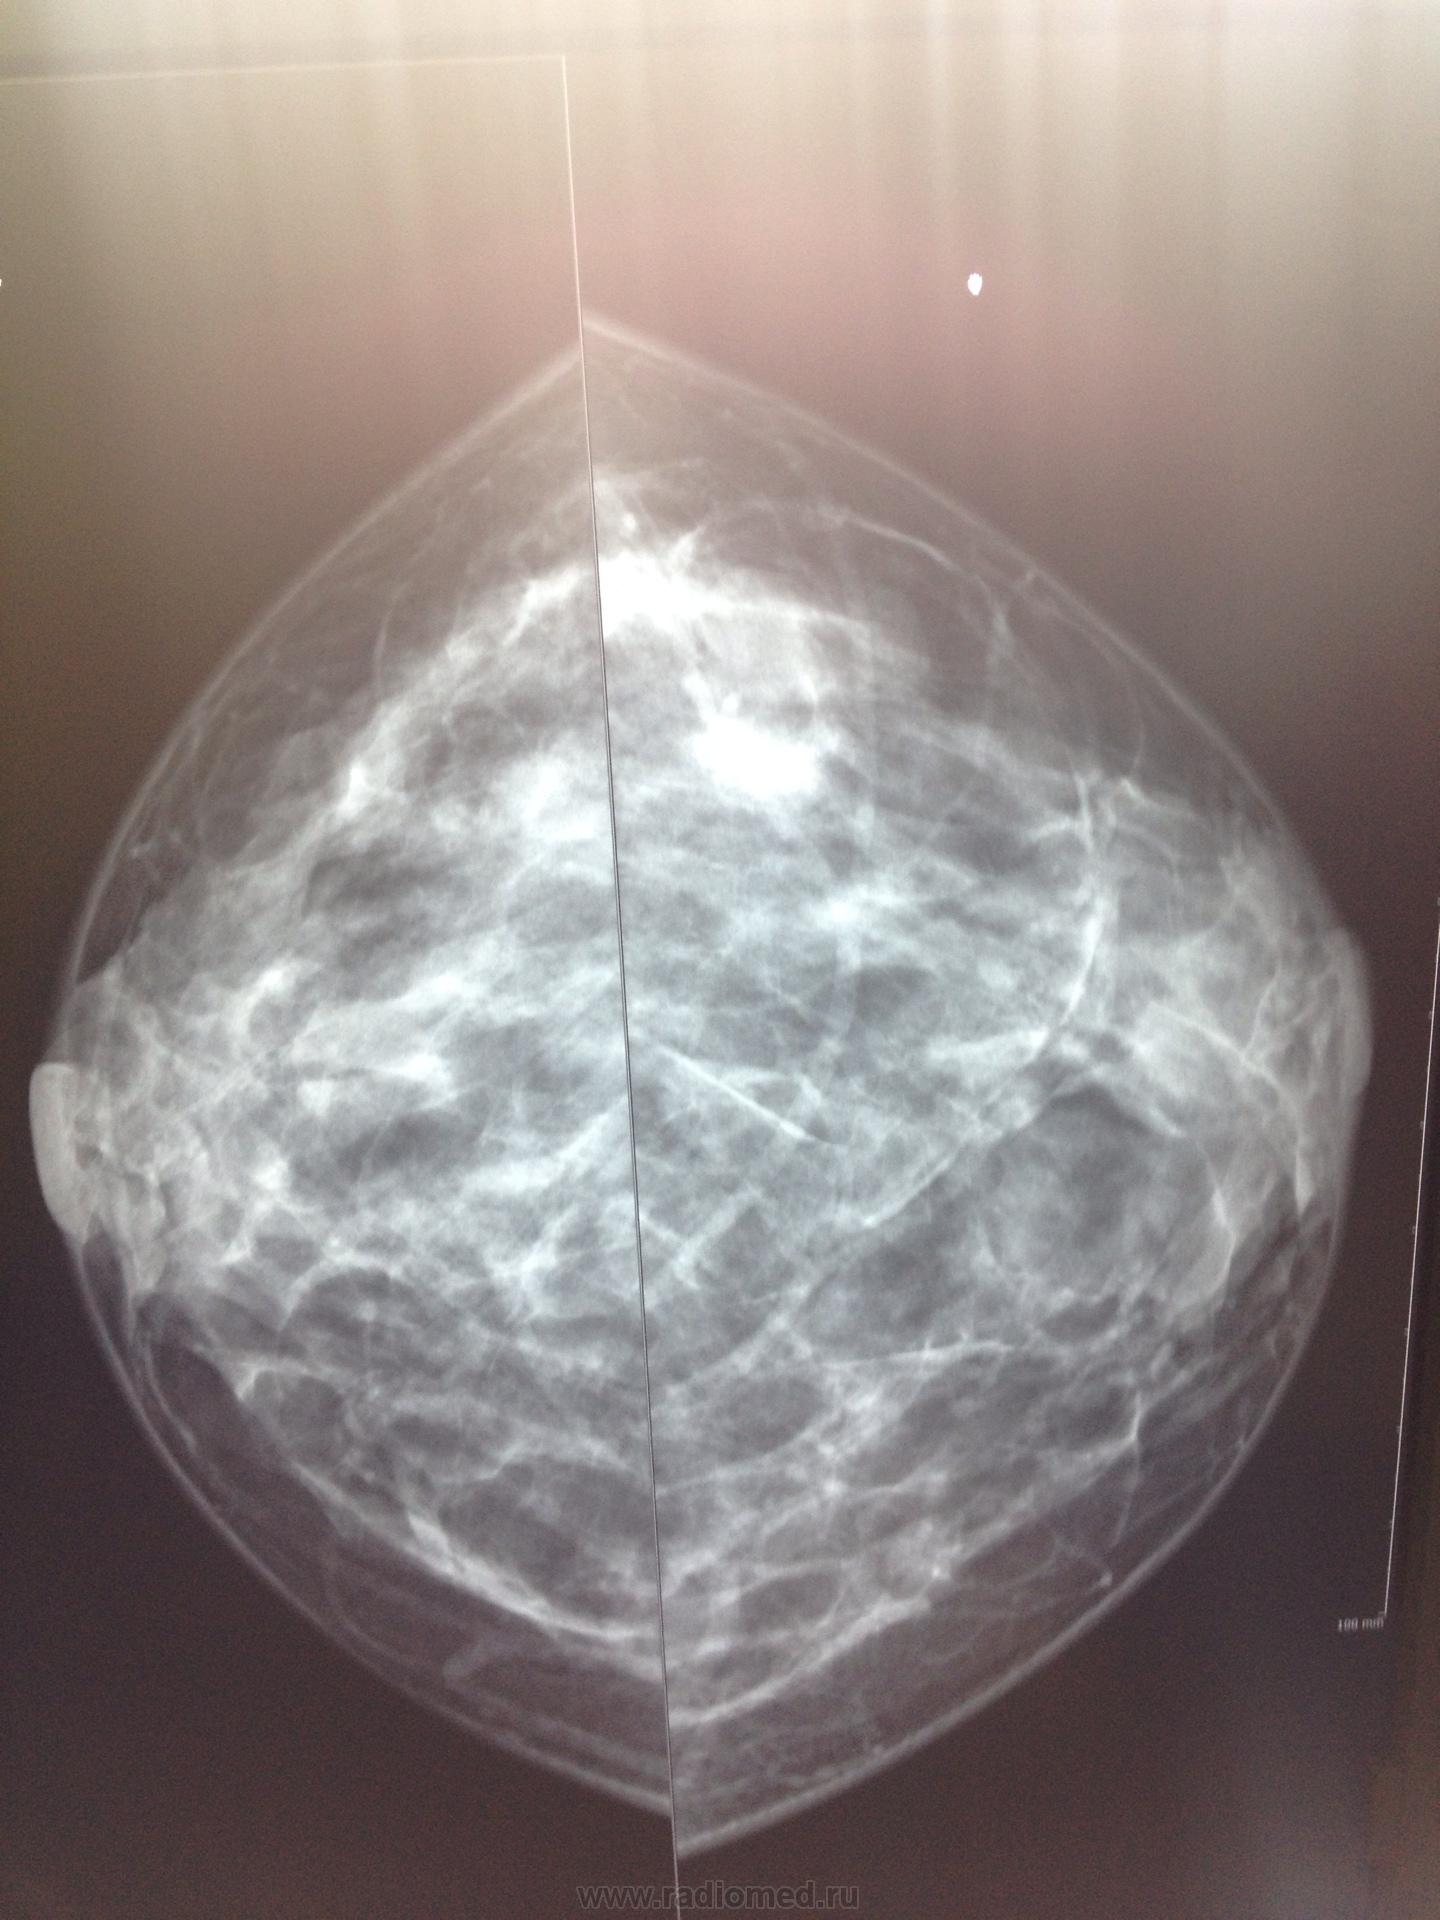

Если хотите дельных комментариев, то придется постараться и научиться добиваться хорошего качества фотографий (в градациях серого, а не белого/черного). По таким снимкам на сайте давать заключение опасно. Но всё же.

- Строение желез 2 типа по Wolfe (площадь фиброгландулярной ткани 25-50%)

- Из патологических признаков: множественные изо- и гиперденсные затенения нерегулярной овальной формы разных размеров (...), с четкими контурами, расположенные разрозненно по всем квадрантам с концентрацией в передних и средних зонах верхне-наружных квадрантов, на фоне утолщения фиброзных трабекул. Бесформенные поля затенения субареолярных зон (фиброз).

-Заключение: категория 2 BIRADS молочных желез - доброкачественные изменения (по типу диффузного фиброаденоза).

На рентгенограммах выполненных в косых проекциях не видно больших грудных мышц- укладка неправильная.